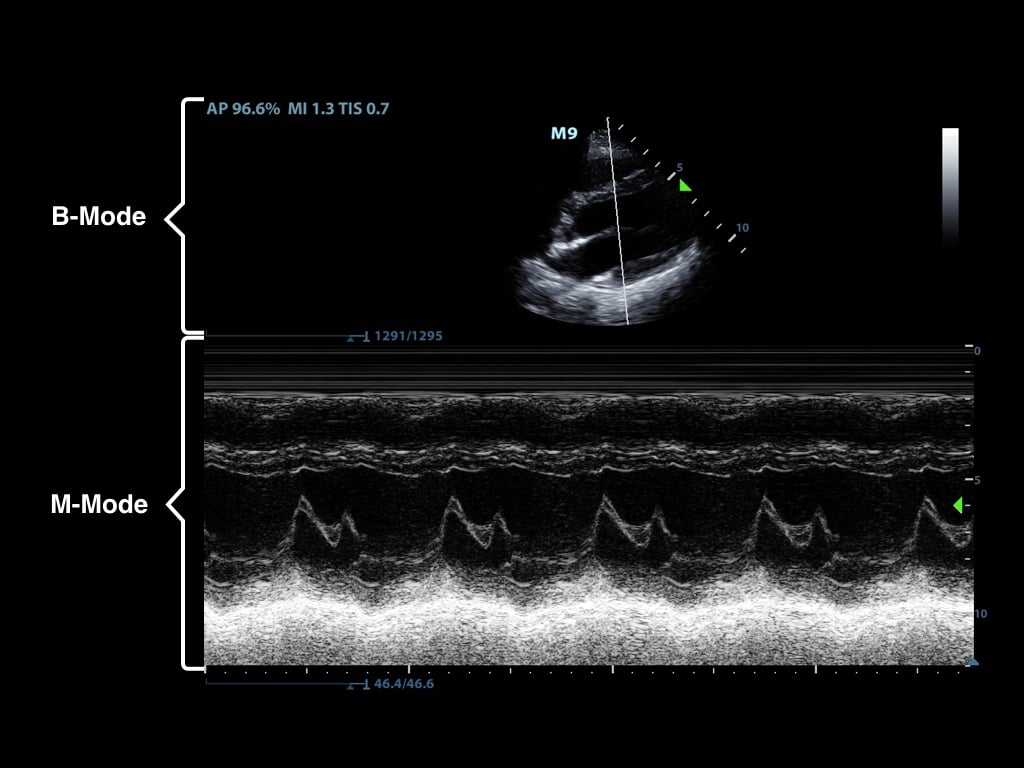

- M-mode (motion mode) captures returning echoes in only one line of the B-mode image displayed over time

- Movement of structures positioned in that line can now be visualized

- Often M-mode and B-mode are displayed together in real-time on the ultrasound monitor (Figure 2, Video 1)

- Figure 2. M-Mode (lower portion of the image) combined with B-Mode image. In this still image the M-mode captures the movement of a particular part of the heart.)

Video 1. M-Mode showing movement of the mitral valve